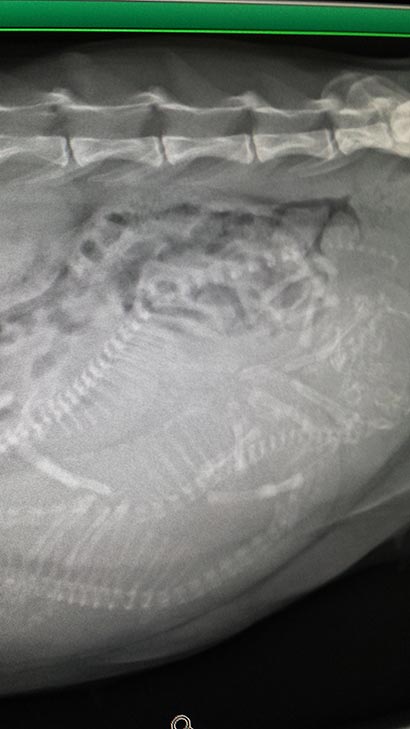

Auf den Röntgenbildern hat man sofort gesehen was los ist. Sie hatte drei Babies.

Da es Ihr immer schlechter ging wurde sie geöffnet, dabei wurde festgestellt das zwei Babies wohl schon länger tot in Ihrem Bauch waren. Ein drittes hat überlebt und wurde zum schöppeln auf eine erfahrene Pflegestelle gebracht.

Hier noch Röntgenbilder: |